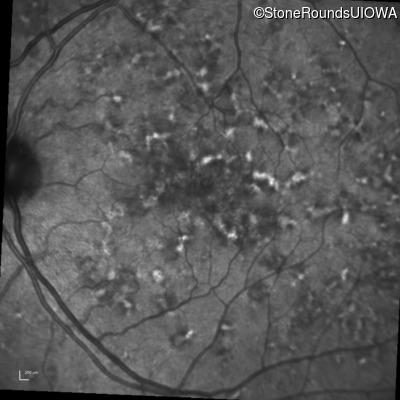

Blue Autofluorescence - Right - 20/20 -1 sc

Exemplar